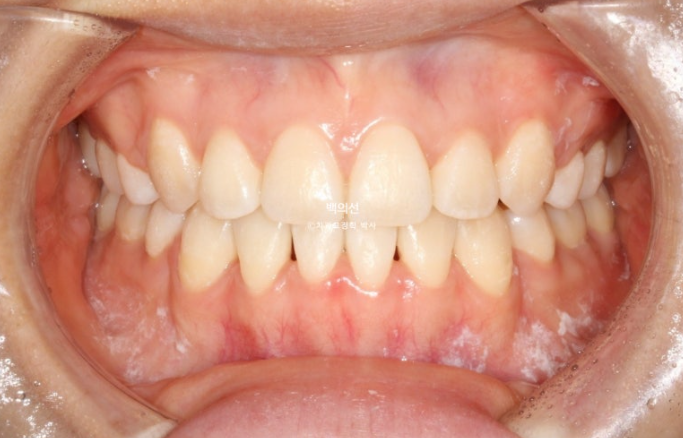

25년 4월까지, 1년 9개월간 치료 후 치료를 마무리 했습니다.

이제 전후 비교 보겠습니다

총 치료기간은 1년 9개월 입니다.

치아끼리 심하게 겹쳐져 있던 부위에 블랙트라이앵글은 아쉽지만 잇몸이 내려가 있었던 다수의 치아들에서 잇몸이 다시 차오른 것을 볼 수 있습니다.

통상 한 번 내려간 잇몸은 다시 차오르지 않는다고 알려져 있지만

잇몸이 내려간 원인이 만약 치아가 자리가 없어 밀려나 있었기 때문이라면, 발치교정을 통해 밀려난 위치에서 안정적인 위치로 움직이는 과정에서 잇몸이 다시 차오를 수 있습니다.

물론 20대 초반의 젊은 성인에서 가능한 이야기지만요.

전반적으로 입매는 잘 유지가 되었습니다.